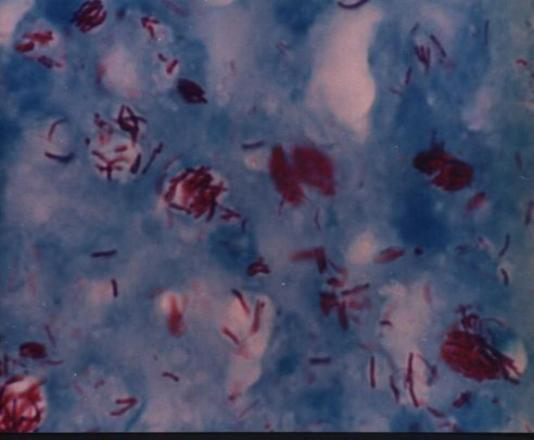

二、麻风病的传染性很厉害吗?麻风分枝杆菌于1873年由挪威学者汉森发现。麻风杆菌其实并不是什么特别强的病原体,离体后虽然仍能存活一段时间,但一般煮沸20-30分钟或高压蒸汽灭菌15-20分完全可以杀死麻风菌。夏天阳光照射2-3小时繁殖能力完全丧失,紫外线照射30分钟活力完全丧失。常用的酒精、碘酒以及紫外线等均可以很好的将其杀死。因此其传染性并没有想象中可怕。

麻风分枝杆菌